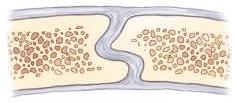

STRUCTURAL ORGANIZATION Several levels of structural organization make up the human body. The lowest level of organization is the chemical level. All chemicals necessary for maintaining life are composed of atoms, which are joined in various ways to form molecules. Various chemicals in the form of molecules are organized to form cells.

The cell is the basic structural and functional unit of all living tissue. Every single part of the body, whether muscle, bone, cartilage, fat, nerve, skin, or blood, is composed of cells. Tissues

Tissues are cohesive groups of similar cells that, together with their intercellular material, perform a specific function. The four basic types of tissue are as follows: 1. Epithelial (ep˝-i-the′ le-al): Tissues that cover internal and external surfaces of the body, including the lining of vessels and organs, such as the stomach and the intestines 2. Connective: Supportive tissues that bind together and support various structures 3. Muscular: Tissues that make up the substance of a muscle 4. Nervous: Tissues that make up the substance of nerves and nerve centers

When complex assemblies of tissues are joined to perform a specific function, the result is an organ. Organs usually have a specific shape. Examples of organs of the human body are the kidneys, heart, liver, lungs, stomach, and brain.

A system consists of a group or an association of organs that have a similar or common function. The urinary system, consisting of the kidneys, ureters, bladder, and urethra, is an example of a body system. The total body comprises 10 individual body systems. Organism

The 10 systems of the body when functioning together make up the total organism—one living being.

Fig. 1-1 Levels of human structural organization.